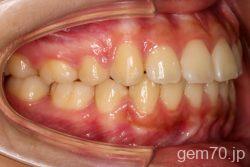

症状:開咬装置:セラミックブラケット | 抜歯世代:10代 | 高校生

診断)開咬

使用装置)マルチブラケット装置

治療方法)抜歯 4|4/4|4

治療期間) 2年4ヵ月 通院回数 27回